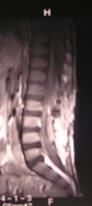

Рис. 44. МР-томограммы позвоночника пациента с гнойным эпидуритом

грудного и поясничного отдела (1,2 слева), послеоперационная рана

заживление вторичным натяжением (справа).